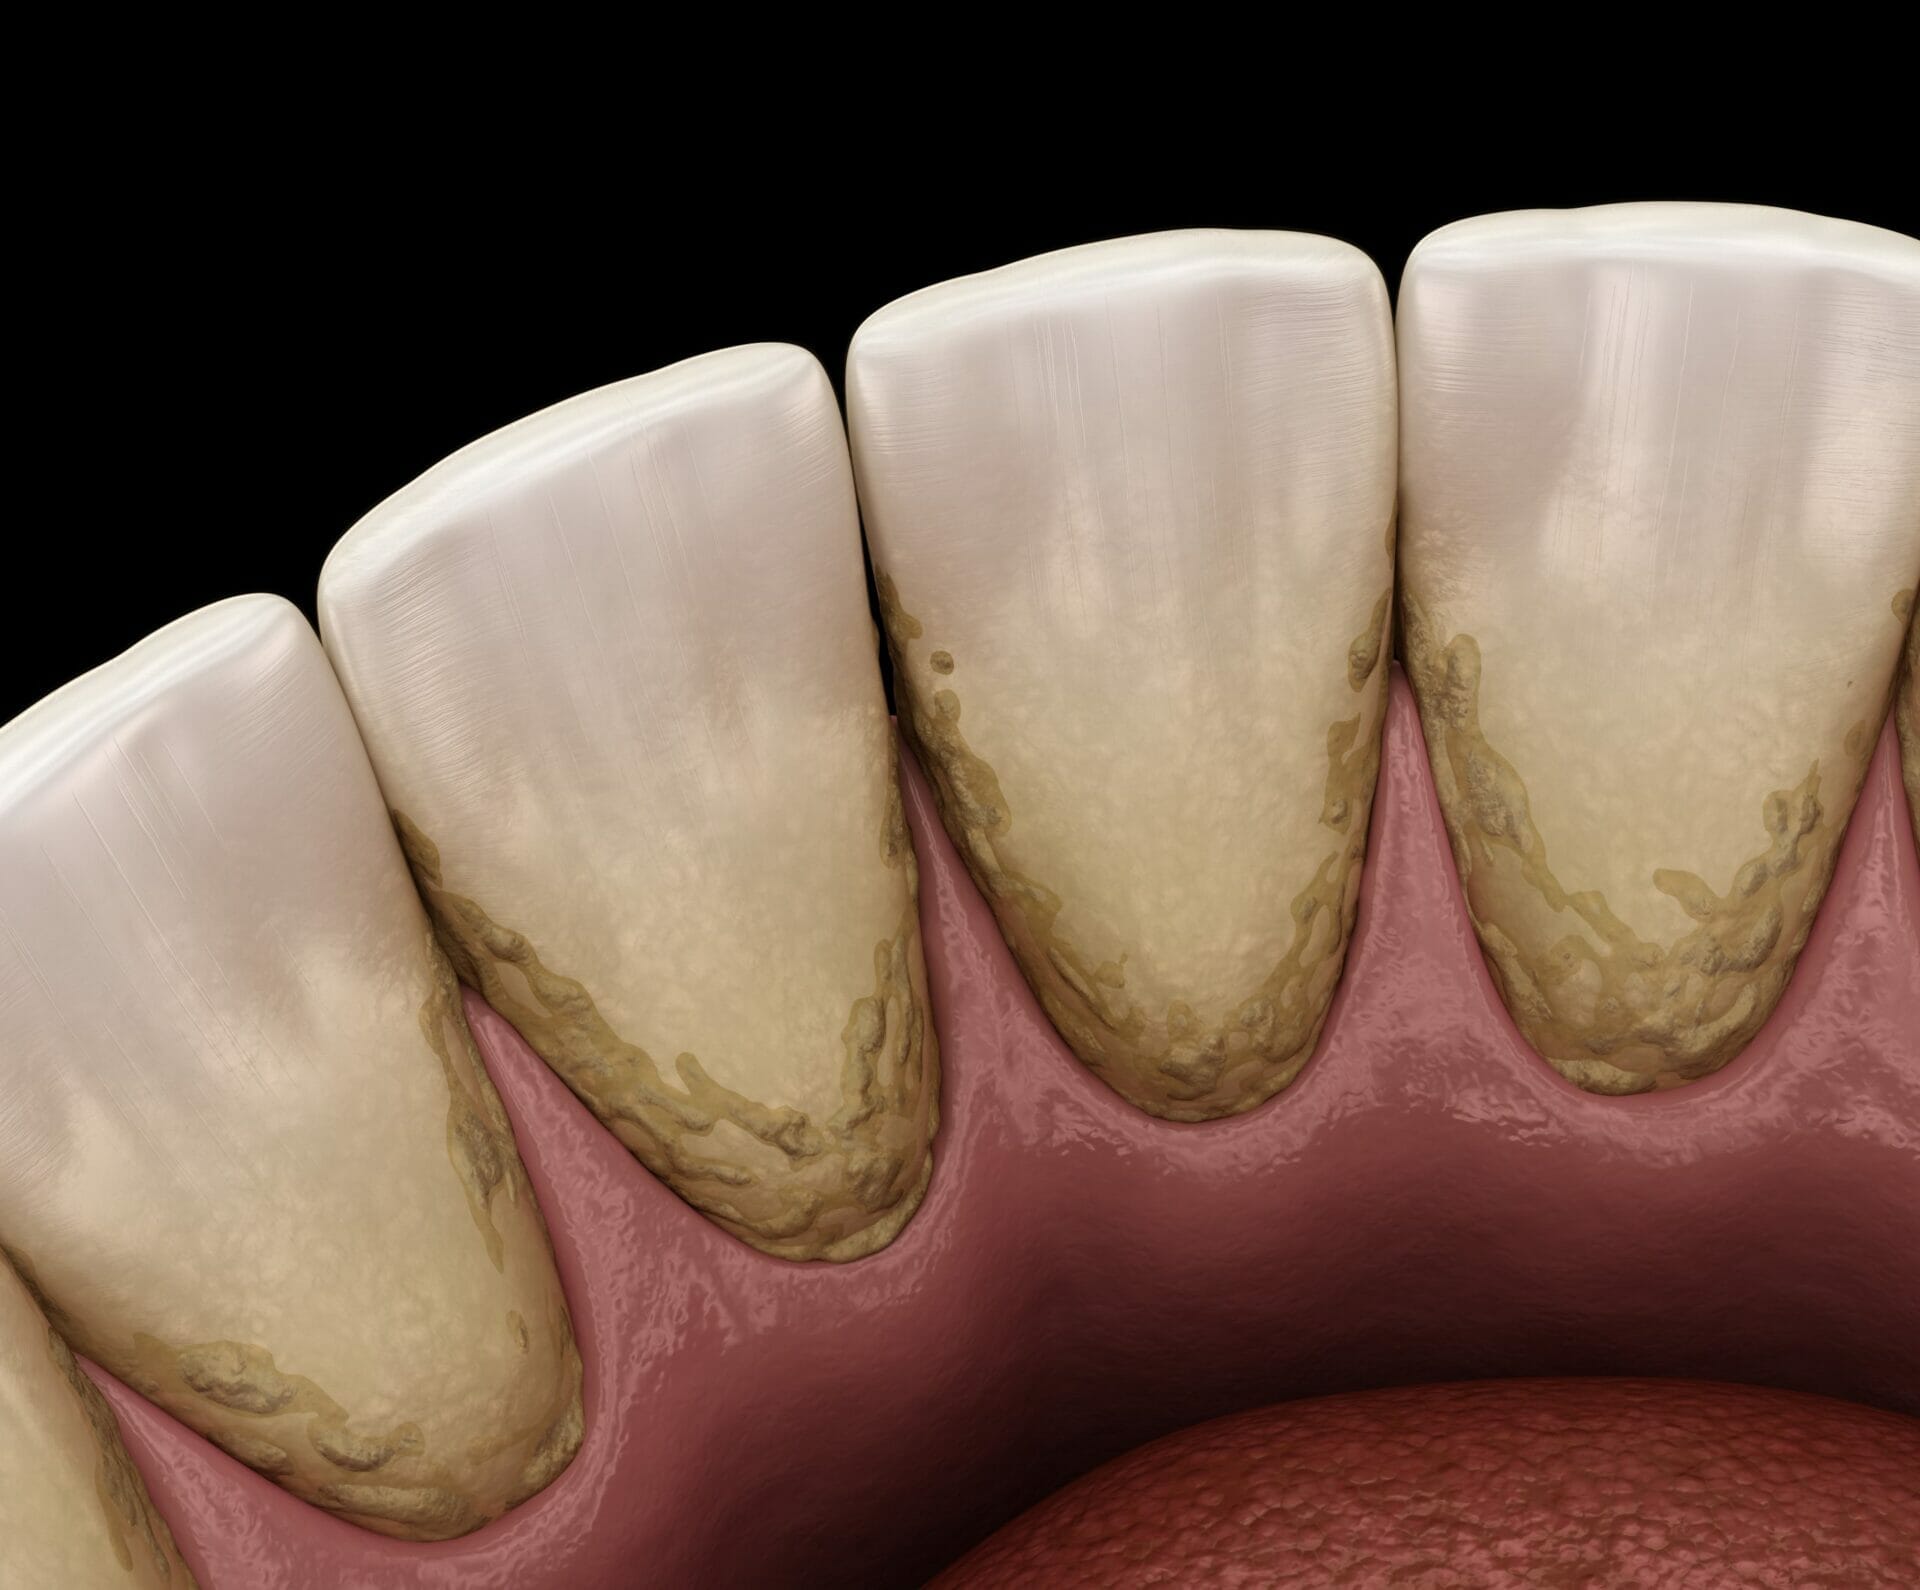

Структура зубов изнутри: фотографии и объяснения

Раздел: Фотомир